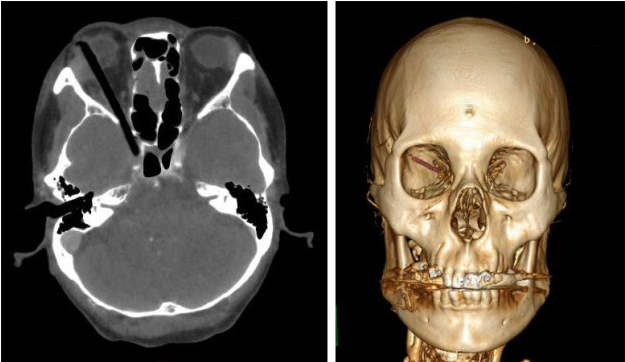

动。外院颅脑CT提示右眶内低密

度异物贯通右侧眶腔,经由眶上

裂侵入右侧海绵窦。异物如长期

治疗团队紧急请来急诊科、影像

科联动,在最短时间内完善了相

关影像学检查。脑血管CTA检查

提示异物侵及右侧海绵窦,颈内

动脉受压向内侧移位,但管壁光

滑,具有急诊手术条件。在急诊